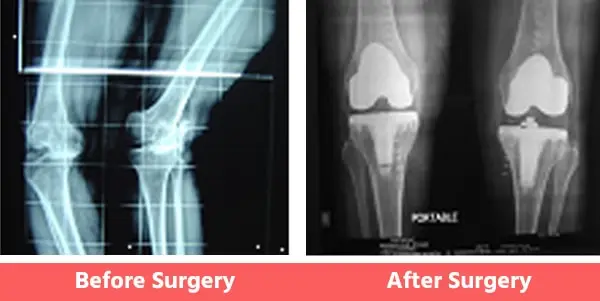

People may have certain deformities of the knee which include bow legs (varus), knock knees (valgus), or even wind-swept legs.

In such cases, the surgeon has to be well-experienced in handling such cases and should also have had considerable experience with revision joint replacement surgeries as well. See below Images.

1. Bow Legs (Varus Knee)

2. Knock Knees (Valgus)

3. Wind Swept Legs

Some Common Deformities

1. Bow legs (Varus)

You can see illustration and X-Ray images shown above already.